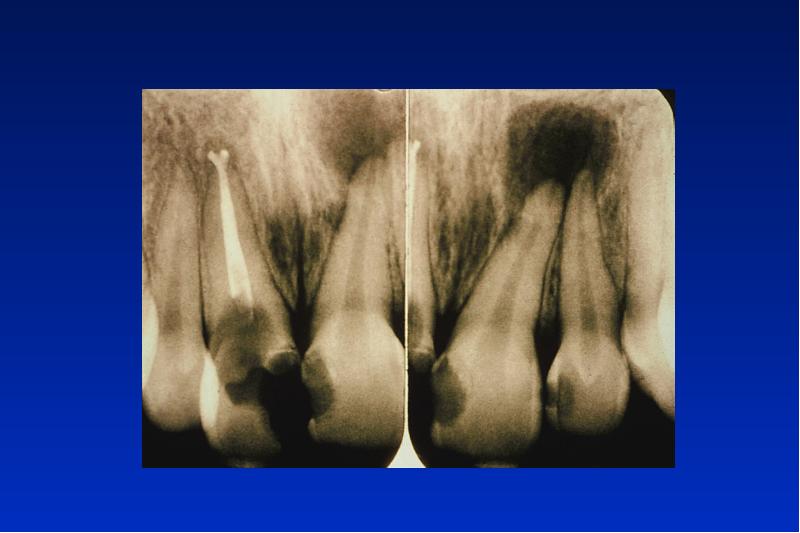

- 4. Radikuläre Zyste Ät: Entzündung Lok: OK, Frontalregion Alter: 30-40

- 5. Pathogenese der radikulären Zyste Karies ----> Pulpitis --->

- 12. Residualzyste eine zahnlose Zyste des Kiefers keine ätiologisch